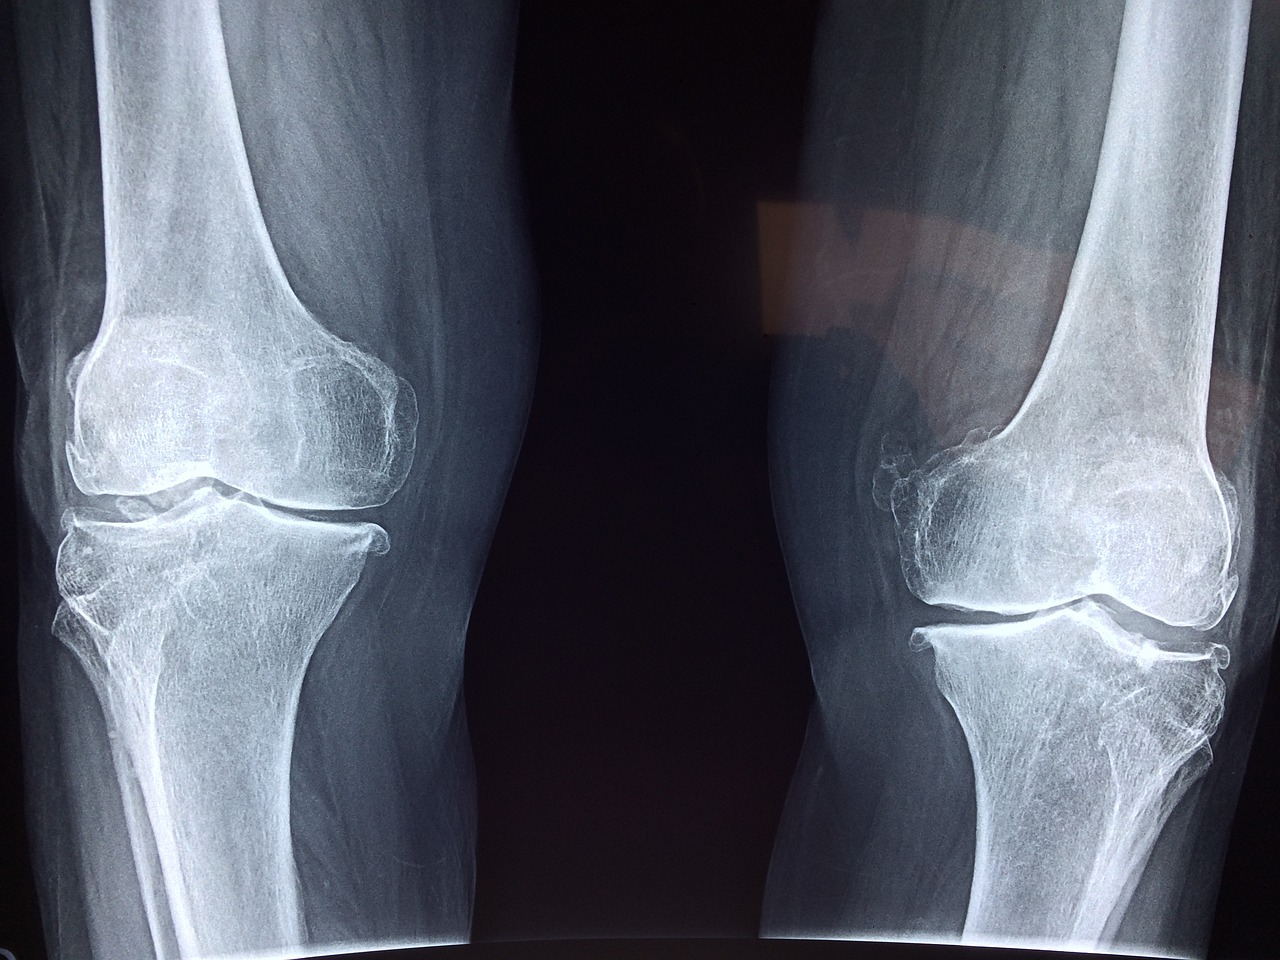

관절염 사진

관절염은 나이가 들면서 발생하는 흔한 질환이지만, 올바른 식습관과 적절한 운동을 통해 예방하고 관리할 수 있습니다. 특히, 관절 건강을 위한 영양소가 풍부한 음식과 무리가 가지 않는 운동을 실천하면 관절염의 진행을 늦추고 통증을 줄일 수 있습니다. 본 글에서는 의학적으로 검증된 관절염 예방 식단과 효과적인 운동법을 소개합니다.